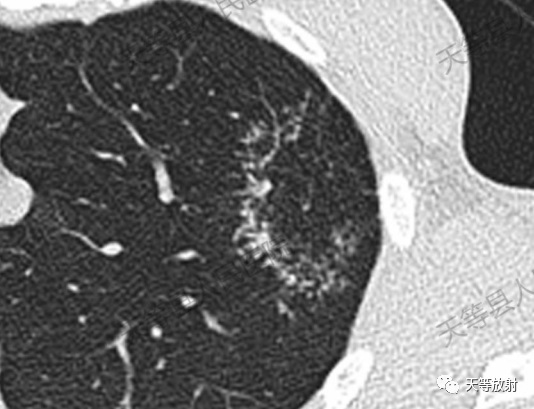

反晕征是一种特殊的胸部 CT 征象,影像学显示中心低密度磨玻璃影,外周为高密度实变影环绕.

结核病形成“反晕征”的病理基础是疏密程度不同的小结节为干酪样肉芽组织,环壁结节密集,结节多为小叶中心结节或小叶间隔结节, 提示淋巴管或支气管播散, 可与其他病理形式肺结核同时存在,即可出现空洞、干酪性肺实变、纤维化钙化等。